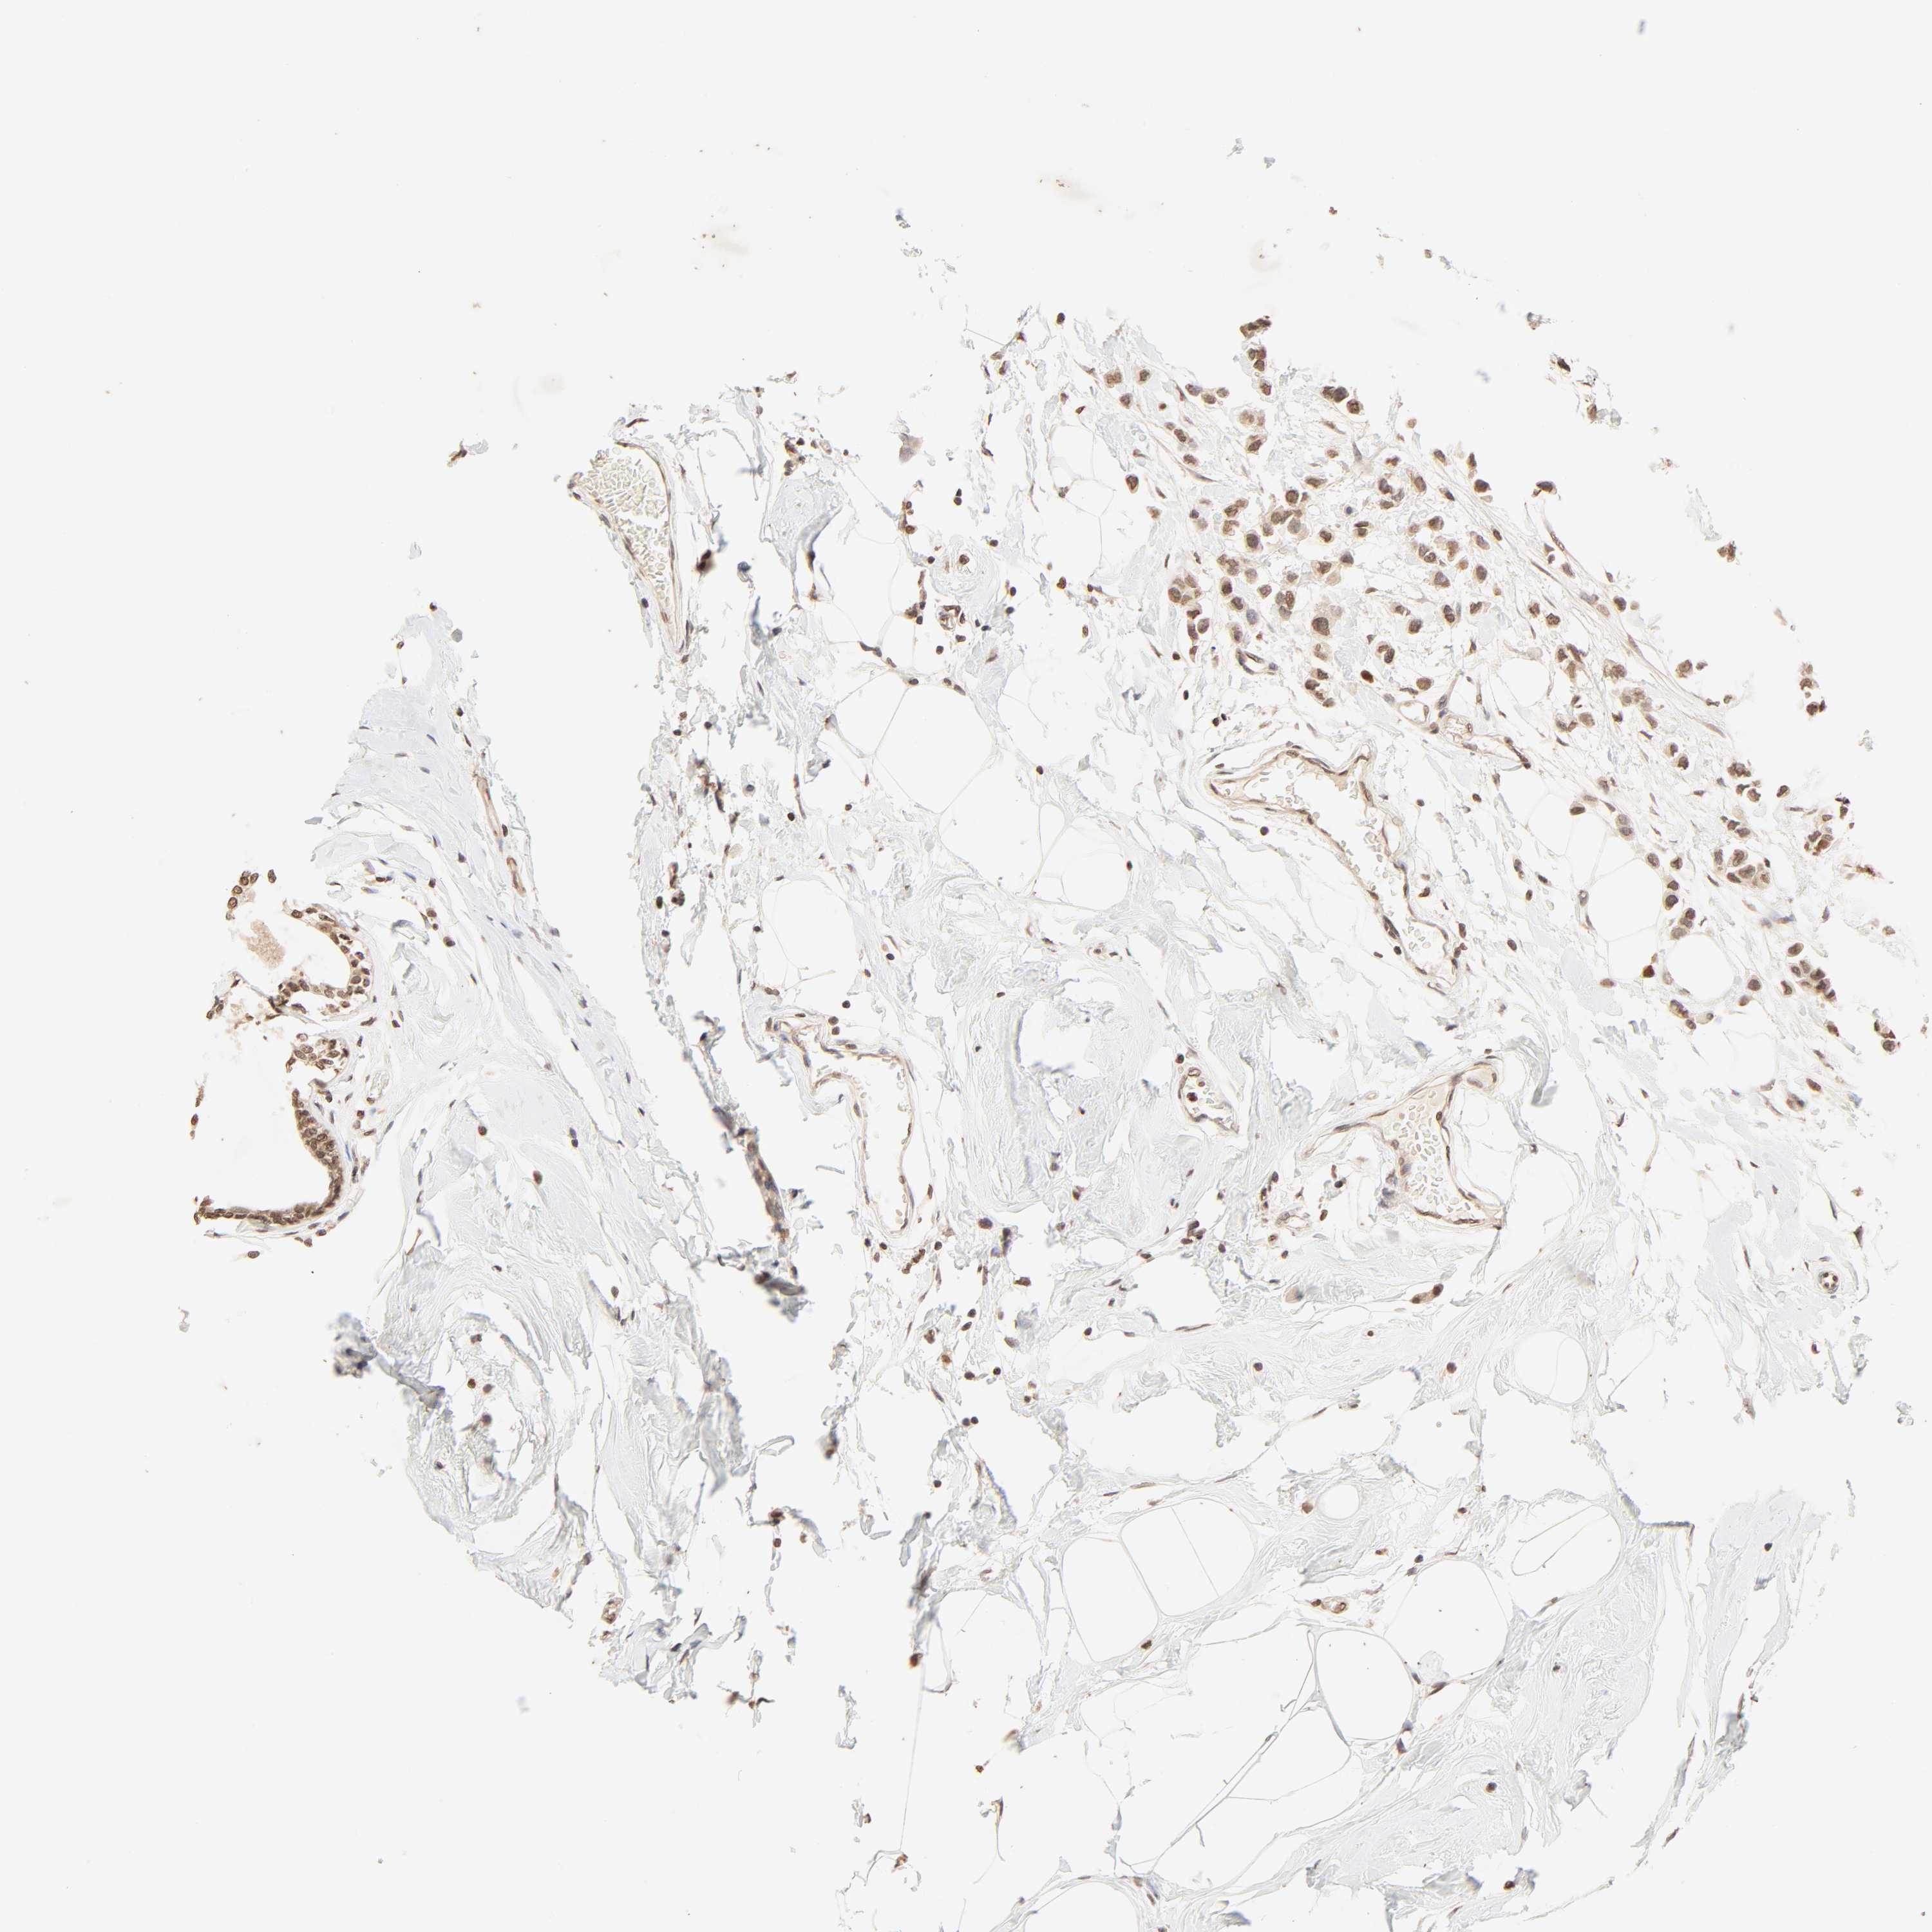

BRCA TCGA BRCA VALIDATION PROTEIN EXPRESSION